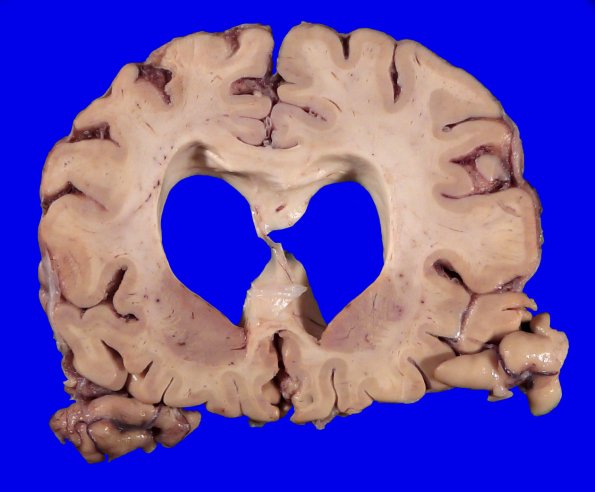

The thickness of the frontal cortex looks generally well preserved although the ventricular dilatation is out of proportion.